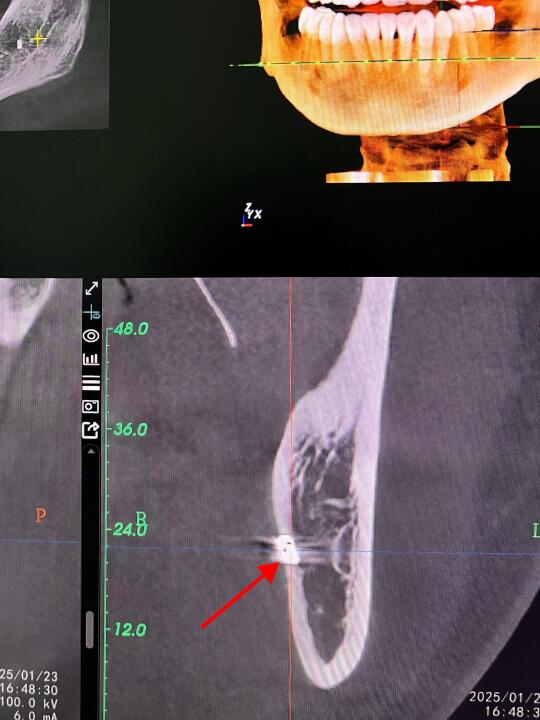

👨🏻⚕️今天有个美女过来找锤哥拔牙~ 👨🏻⚕️美女说有上次在诊所拔牙的牙片,锤哥看后说“还是在我们科重新拍一张牙片吧~” 🤣不拍不知道,一拍吓一跳,拍片后发现美女上次拔牙后,骨头里有个高密度影~ 👨🏻⚕️以锤哥多年的工作经验来看,这好像是折断在里面的「钻头」 🫣好在锤哥先复查了一个牙片,不然还真有点说不清了,话说那个诊所也是🐮B,骨头里留下这么长一根钻头,都不跟患者说,也不想办法取出来~ 👨🏻⚕️锤哥在这里奉劝大家,拔牙风险高,且拔且小心❤️啊!